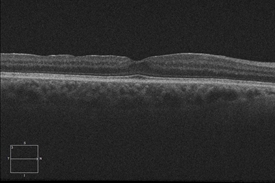

Optical coherence tomography (OCT) is a commonly used and recommended method to noninvasively identify and monitor VMT syndrome. This technology captures cross-sectional images of the retinal layers, including the surface, and allows physicians to evaluate the degree to which vitreomacular tractional forces are distorting the retinal structure.

- Watchful waiting and regular monitoring with OCT is often used for patients whose symptoms do not warrant active intervention. Some cases of VMT may spontaneously resolve.